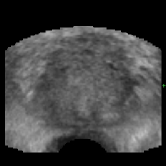

Refer to caption

Figure 7: Intensity shift correlation model. Fig. (a) shows the floating volume, Fig. (d) the fixed volume (after rigid registration), Fig. (b) the elastic registration with the SSD correlation model and Fig. (c) shows the result with the intensity shift correlation model and inverse consistency constraints. All other parameters were identical for both registrations. The SSD driven registration is incorrect because of various local intensity shifts that are caused by the difference in probe pressure between the acquisition of the fixed and the floating images. The intensity shift correlation model correctly handles this problem and converges to the physically correct result.